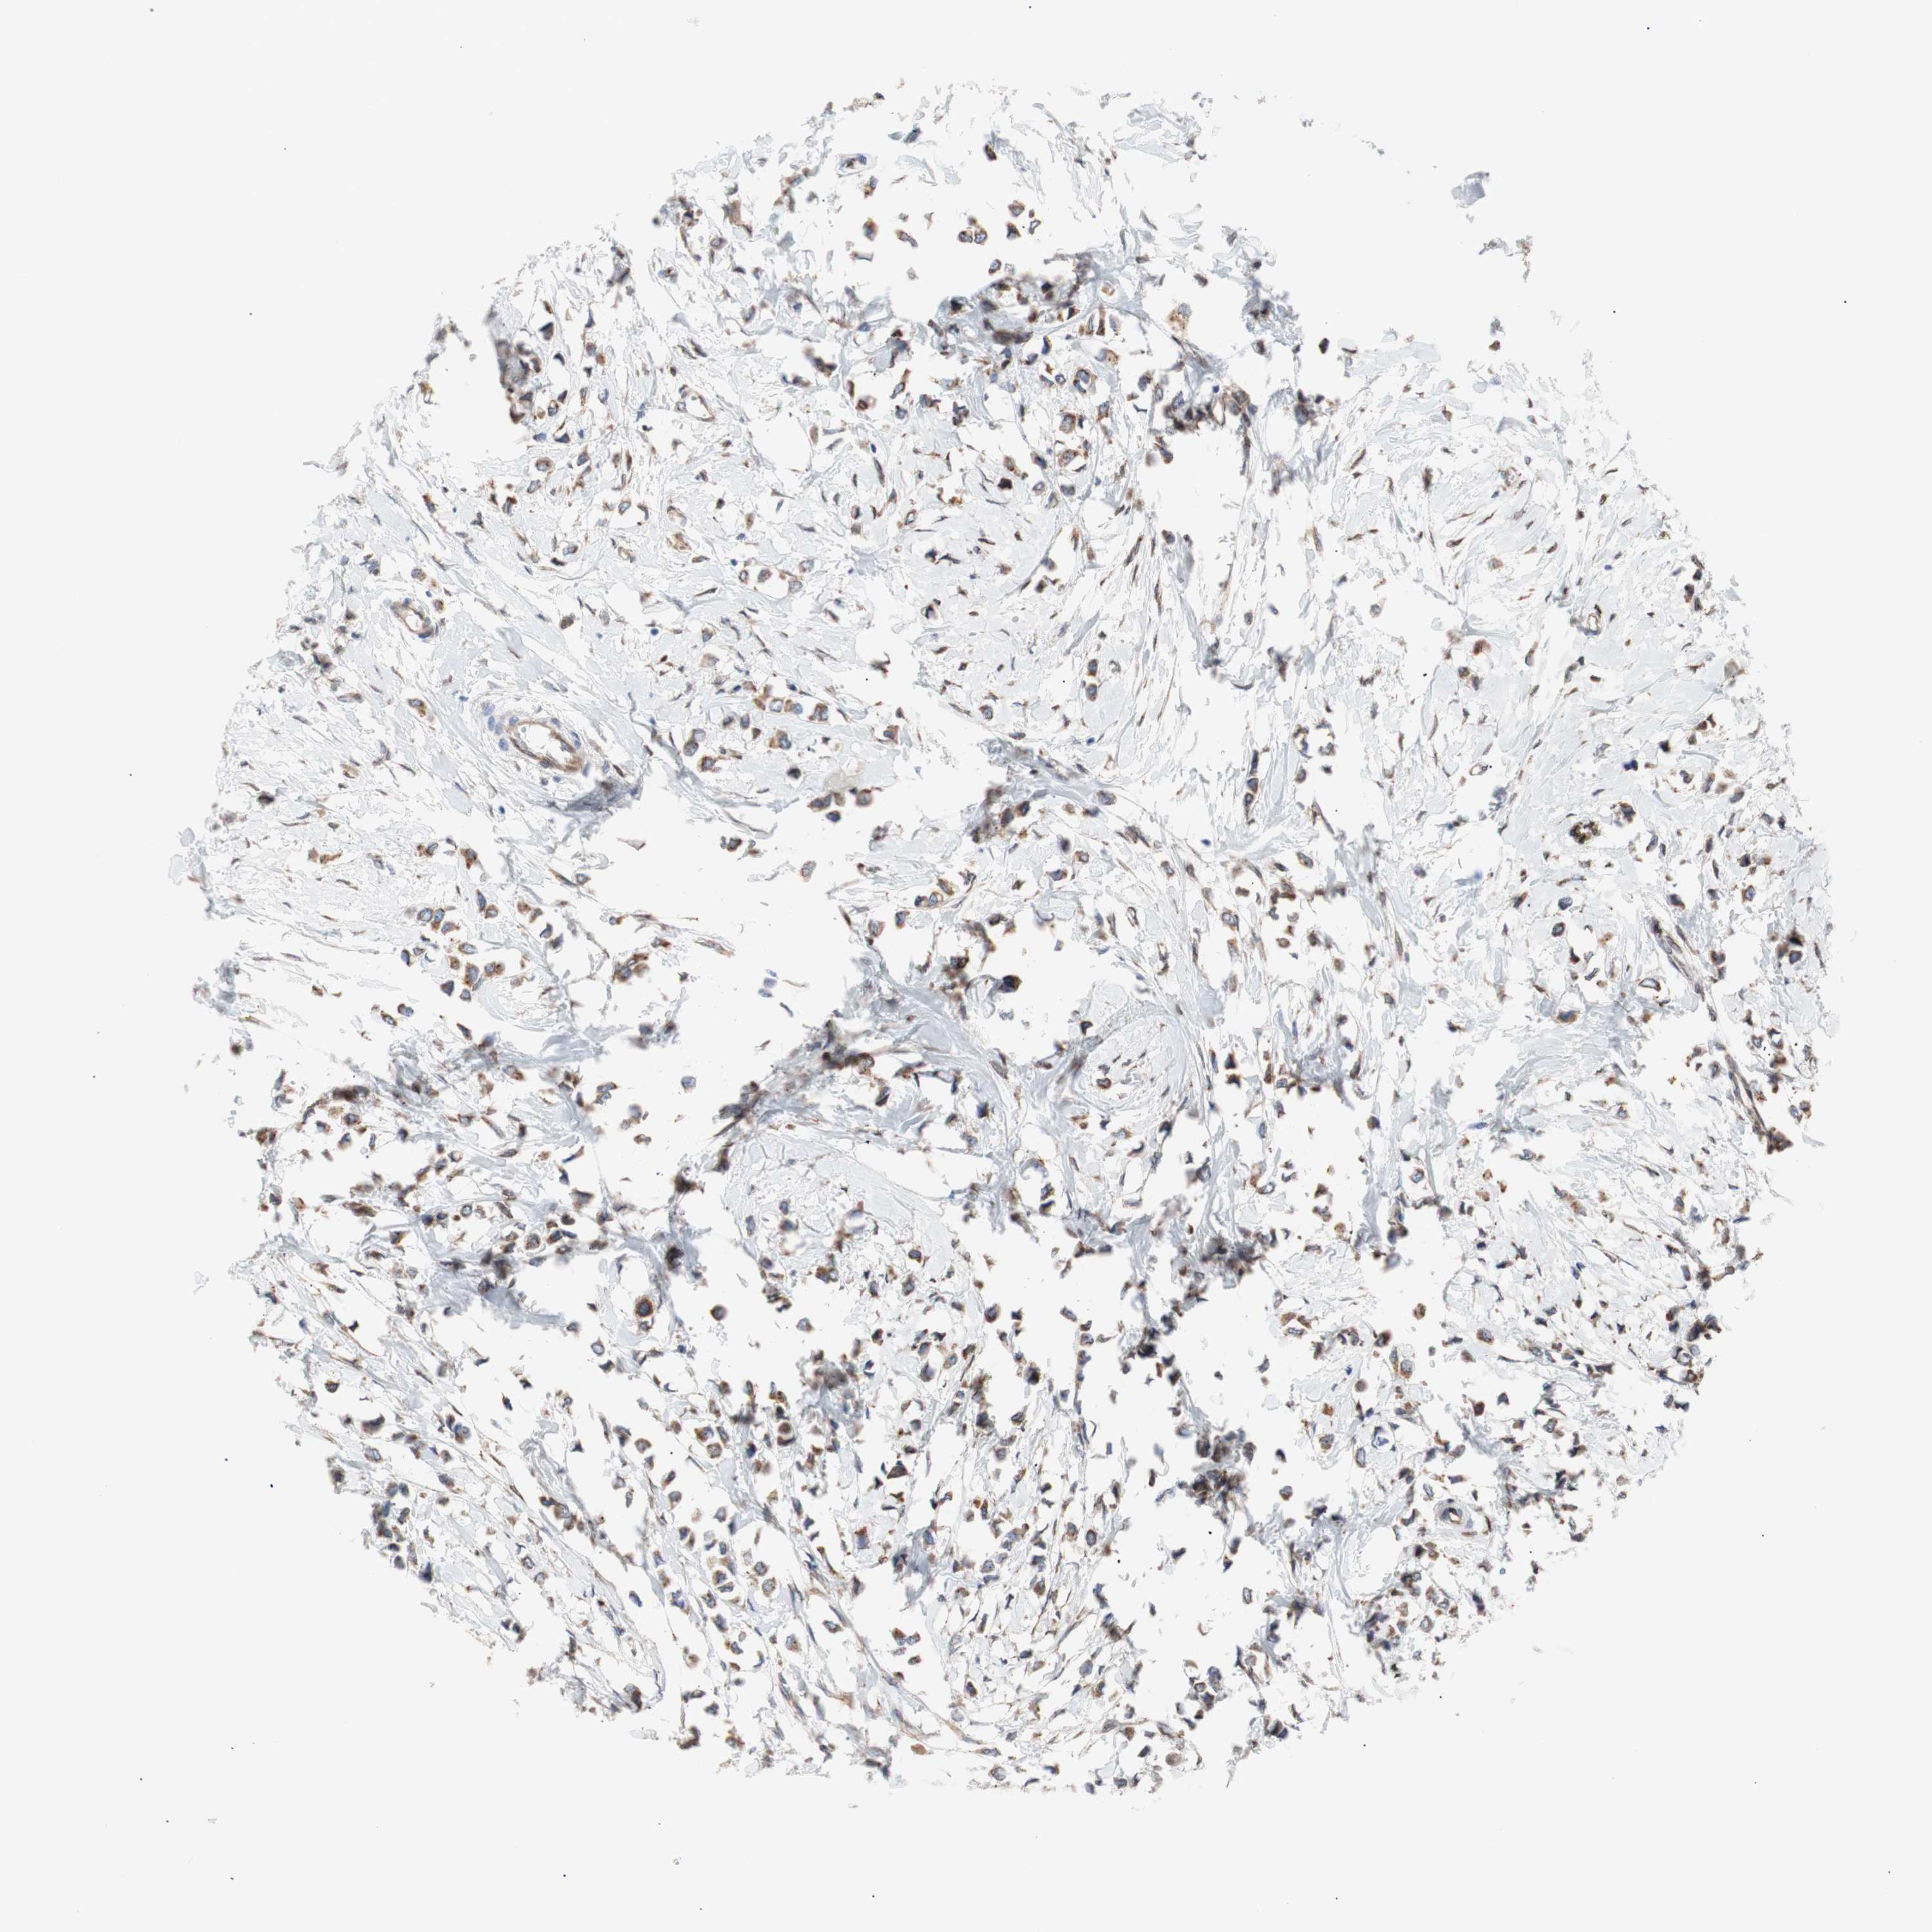

CANCER BREAST CANCER Show tissue menu

BRCA TCGA BRCA VALIDATION PROTEIN EXPRESSION

Breast cancer

Human cancer

ERLIN1 is not prognostic in Breast Invasive Carcinoma (TCGA)